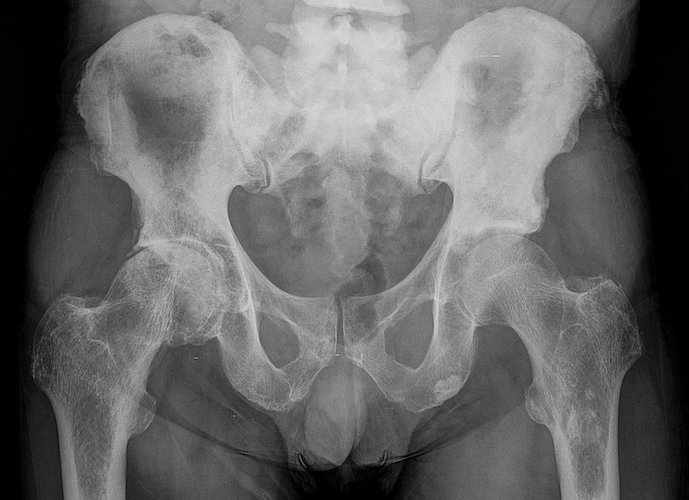

- La radiographie standard : C'est le seul examen complémentaire incontournable . La radiographie standard est suffisante dans la majorité des cas, depuis l'étape du diagnostic jusqu'à la mise en place de la prothèse totale de hanche.

Initiée par le médecin traitant, le rhumatologue ou volontairement, cette première consultation permettra de confirmer le diagnostic d'arthrose de la hanche (coxarthrose), d'évaluer la sévérité de l'arthrose et de programmer un projet thérapeutique à court, moyen et long terme. Il est conseillé de se rendre à cette consultation, avec au minimum une radiographie du bassin et des hanches, de face et de profil. Ces radiographies devront être réalisées en charge (debout). Cette consultation est relativement codifiée et comporte des étapes essentielles :